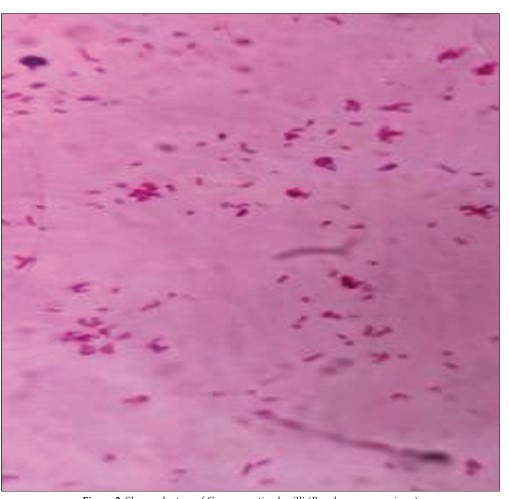

Pseudomonas Aeruginosa in an Immunocompetent Individual with Acute Tonsillitis; An Uncommon Finding: A Case Report

The tonsils, lymphoid tissue located in the throat, serve as the first line of immunedefense against pathogens entering the oral cavity. Tonsillitis is a common presentation in ENT clinics, affecting both children and adults. Staphylococcus aureus and Streptococcus are the most frequently isolated bacteria from throat swab cultures in these cases. While Pseudomonas aeruginosa is not a rare pathogen in acute or chronic tonsillitis, its isolation from an immunocompetent individual with this condition is uncommon. This case report presents an unusual instance of Pseudomonas bacteremia in a 20-year-old healthy male with acute tonsillitis.